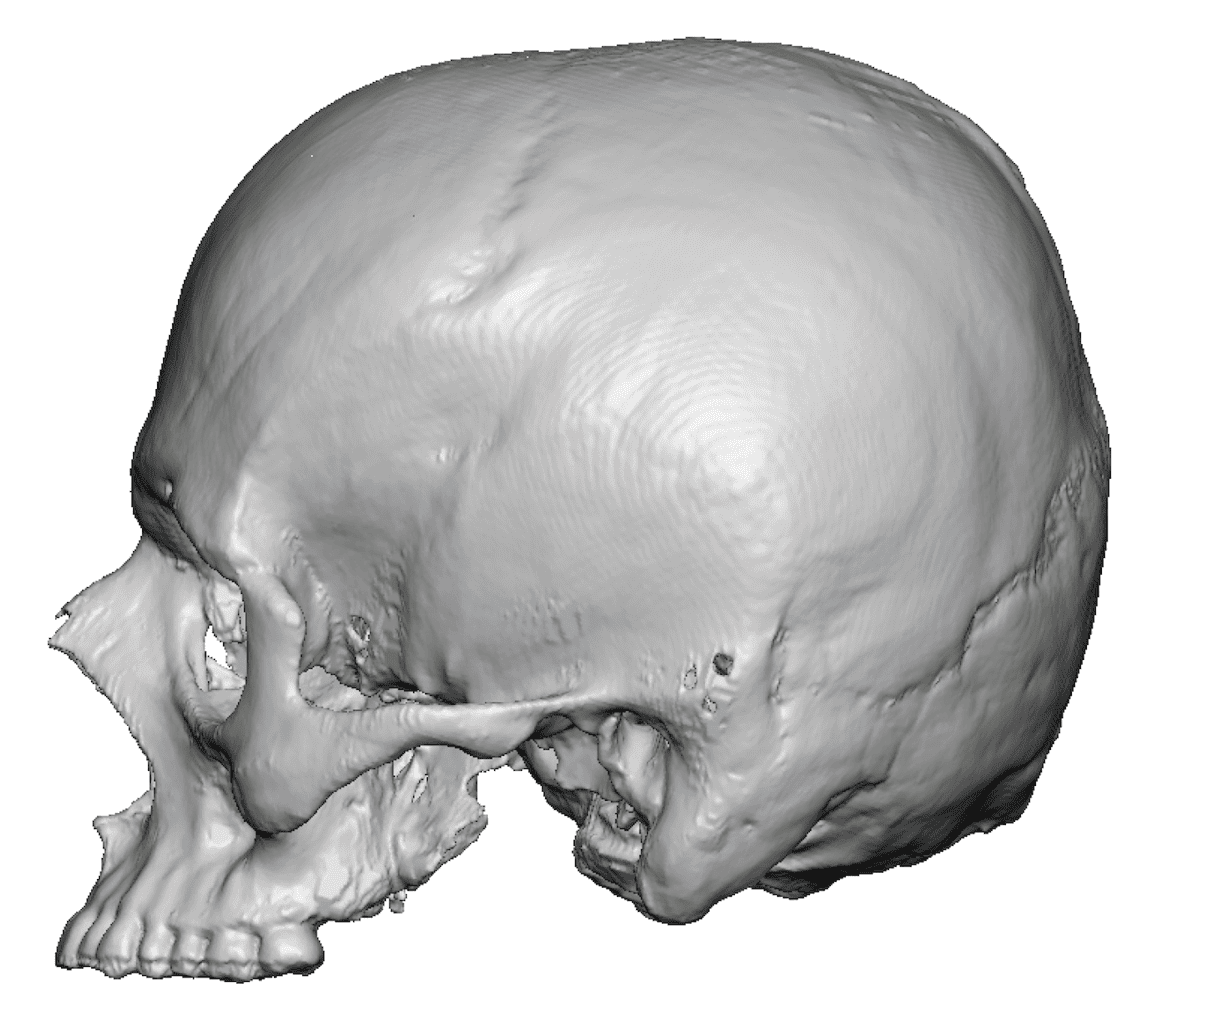

Patient 49

Desire for further skull augmentation after a primary skull implant.

Five years after an initial custom skull implant placement a new custom skull implant that increased the volume by 35% was placed.

Desire for further skull augmentation after a primary skull implant.

Five years after an initial custom skull implant placement a new custom skull implant that increased the volume by 35% was placed.